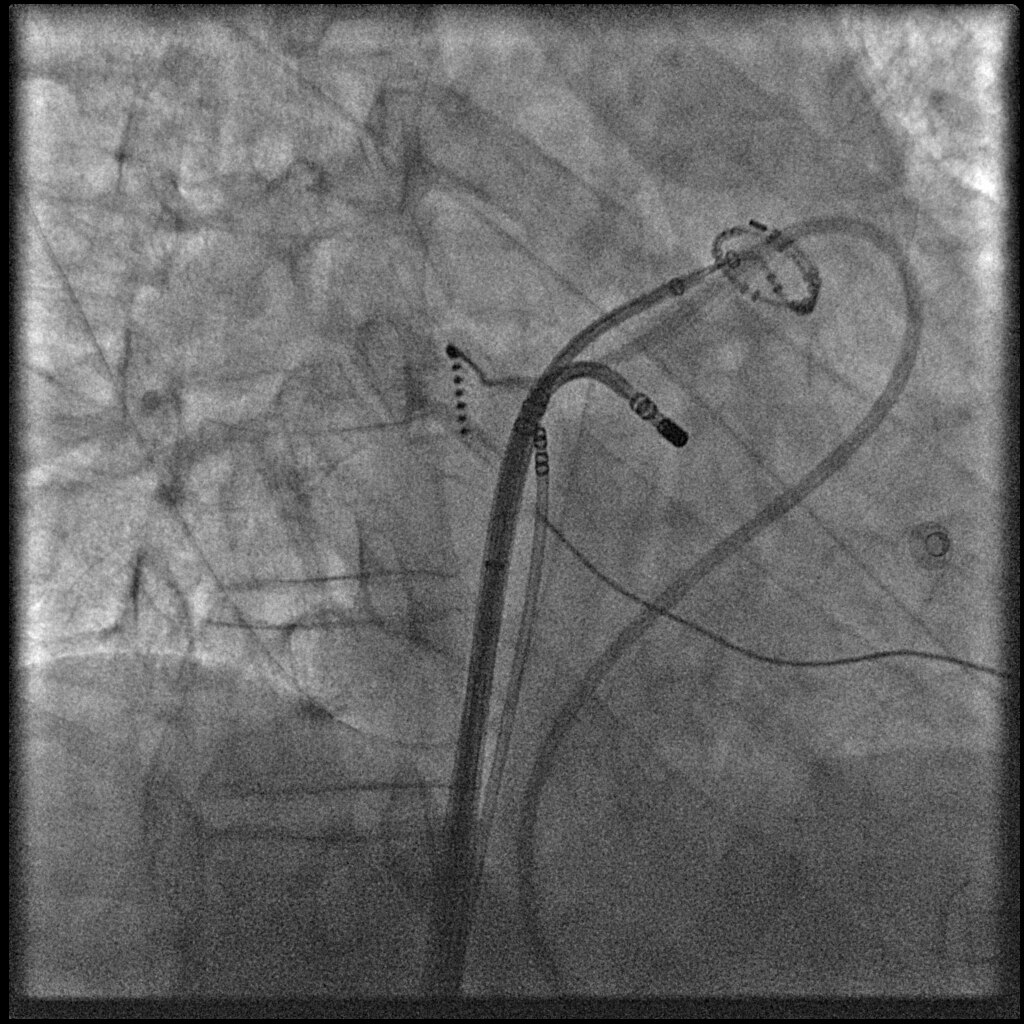

Моторизованное движение по 3-м осям делает даже наиболее сложные проекции легкодоступными. L-штатив вращается вокруг вертикальной оси на +100° (+/- 95° моторизованно). Комбинация движений С-шатива и L-штатива обеспечивает ангуляцию краниально и каудально от -50° до +45°. Изгиб С-штатива обеспечивает вращение в диапазоне -117°/+105° RАО/LАО. Глубина изгиба С-штатива — 107 см (42″) при позиции L-штатива на 0° обеспечивает поперечное покрытие тела большинства пациентов.

Компактная дека стола Оmega V с углепластиковой ламинированной структурой обеспечивает максимальную жесткость при наименьшем поглощении и рассеянии излучения в сочетании с возможностью повышенной ангуляции системы. Ротация деки стола +180 градусов вокруг вертикальной оси обеспечивает легкость укладки пациента, прекрасный доступ при выполнении анестезии, пункции верхних конечностей, а также быстрый доступ к пациенту в экстренных ситуациях. Дека стола способна поддерживать вес пациента до 204 кг. Длина деки — 333 см; ширина в области туловища пациента — 46 см. Удлиненная дека стола позволяет обеспечить наличие места для расположения проводников и катетеров. Она также может быть использована как стерильная рабочая зона без дополнительной тележки, необходимой для скальпелей, катетеров и пр.